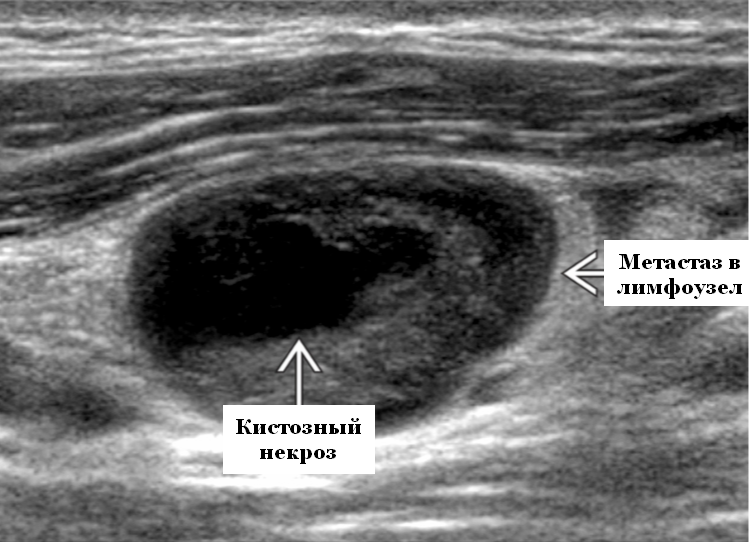

Мезентериальные лимфатические узлы: УЗИ и диагностика